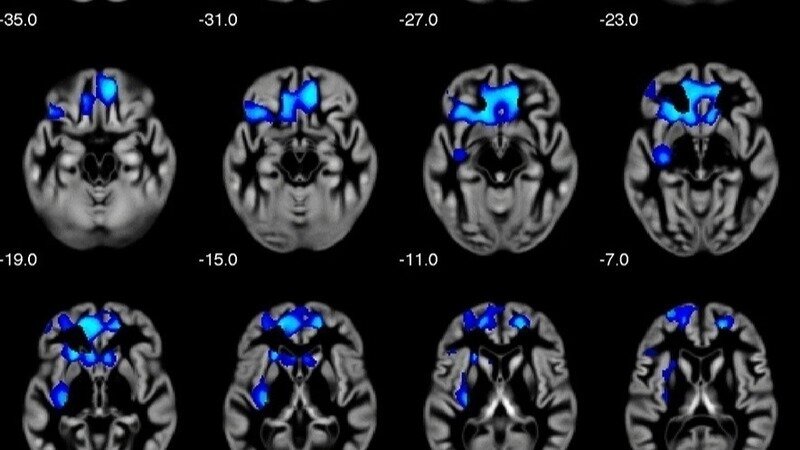

Recent advancements in technology now provide us with non-invasive brain scans, such as non-radiative X-ray examinations, which can help determine brain grey matter distribution. When combined with sophisticated artificial intelligence algorithms, these tools offer a promising avenue for detecting behavioral tendencies associated with NPD. By understanding and quantifying grey matter distribution, researchers believe it is possible to identify patterns indicative of narcissistic traits, which could vastly improve diagnosis and intervention strategies.